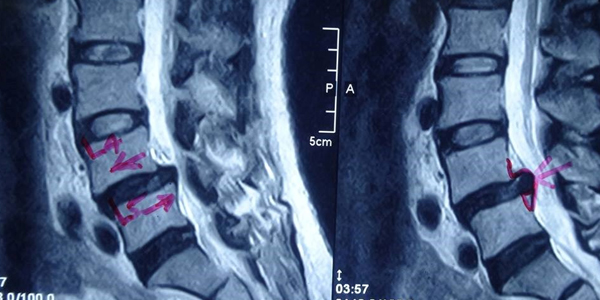

– Cộng hưởng từ (MRI):

+ Cộng hưởng từ là công cụ lý tưởng để đánh giá tổn thương về mô mềm và sự chèn ép thần kinh trong trượt đốt sống vùng thắt lưng – cùng. Trên phim cộng hưởng từ, có thể phát hiện các nguyên nhân gây chèn ép thần kinh: đĩa đệm thoát vị, dây chằng dày, các tổ chức xơ sẹo, hẹp lỗ ghép,…

Hình 2: Mô phỏng hình ảnh trượt đốt sống trên MRI